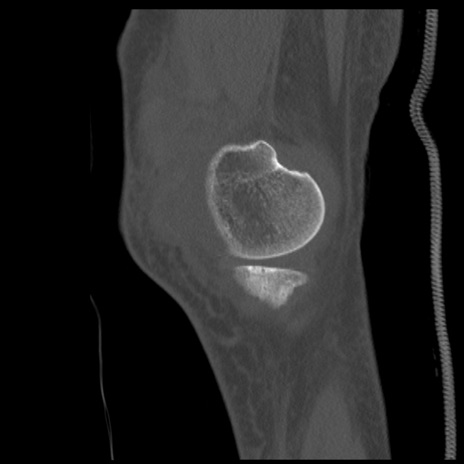

症例28 右膝関節CT(矢状断像)

右膝関節CT